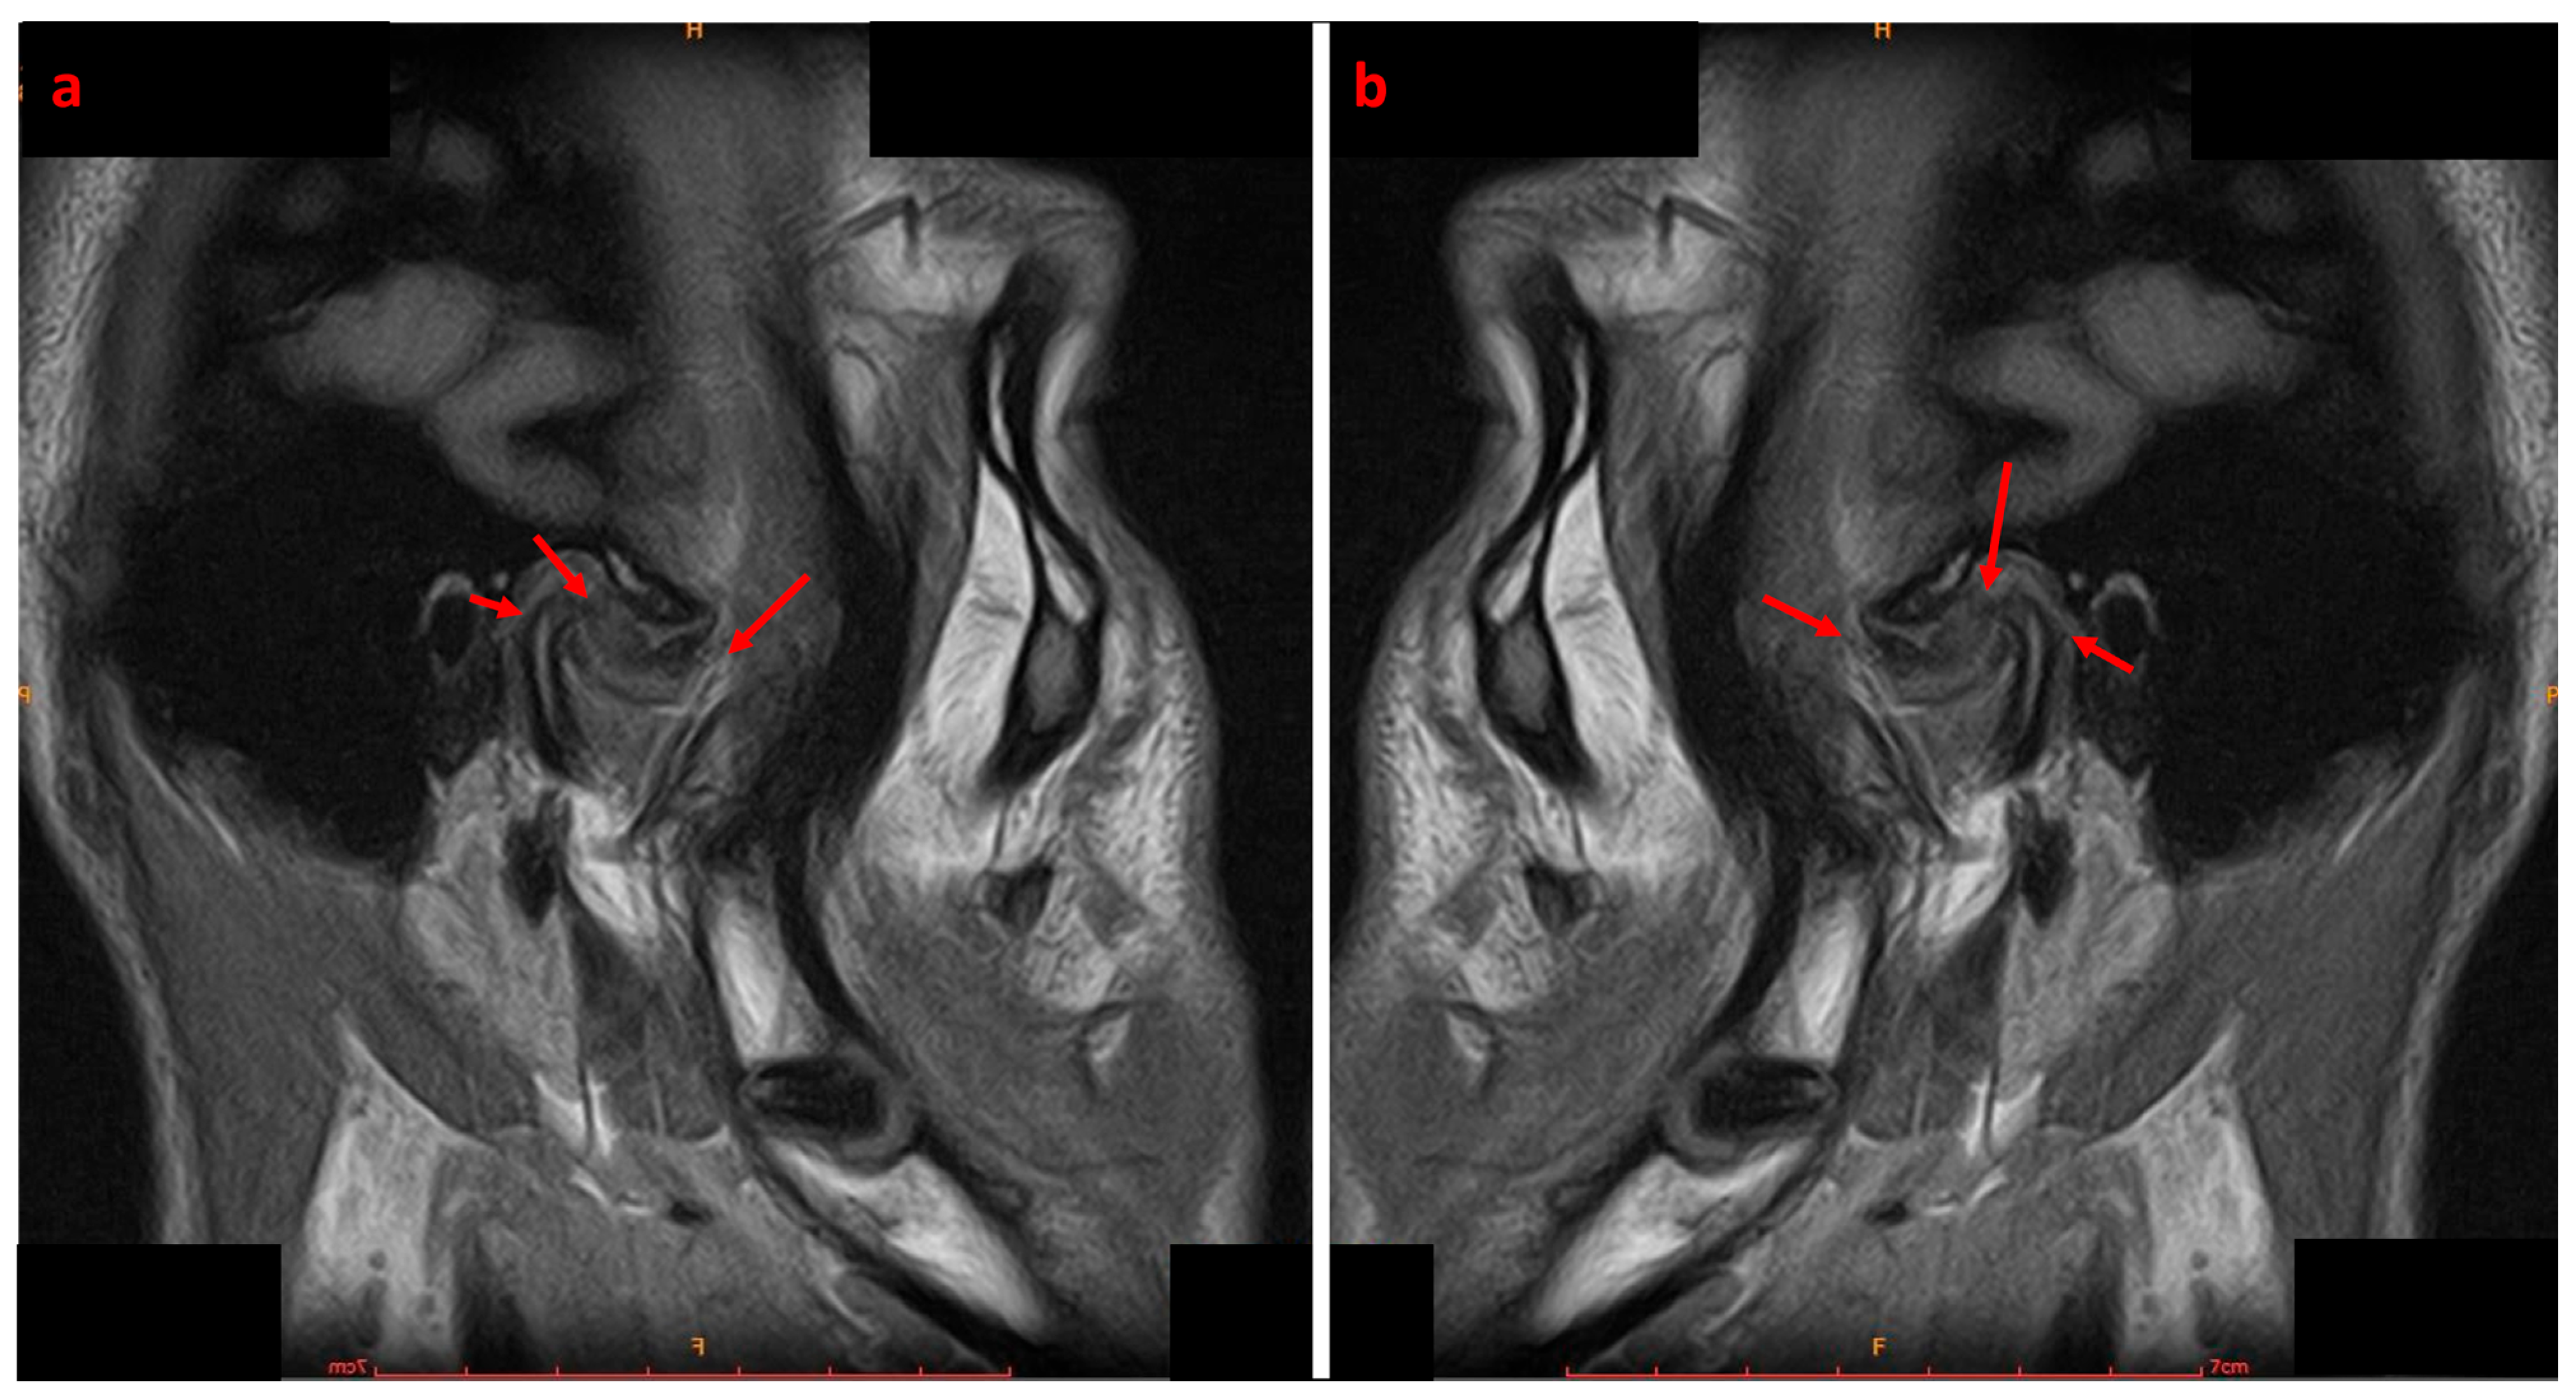

2.4. Diagnosis and Treatment Planning

- Hasan, N.M.A.; Abdelrahman, T.E.F. MRI evaluation of TMJ internal derangement: Degree of anterior disc displacement correlated with other TMJ soft tissue and osseous abnormalities. Egypt. J. Radiol. Nucl. Med. 2014, 45, 735–744. [Google Scholar] [CrossRef]